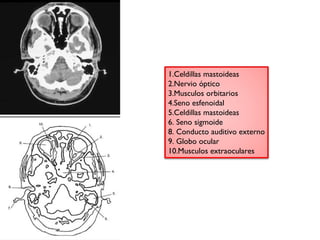

1.Celdillas mastoideas

2.Nervio óptico

3.Musculos orbitarios

4.Seno esfenoidal

5.Celdillas mastoideas

6. Seno sigmoide

8. Conducto auditivo externo

9. Globo ocular

10.Musculos extraoculares